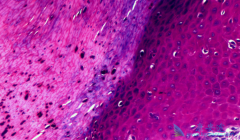

什么是恶性黑色素瘤?恶性黑色素瘤是皮肤癌,是恶性程度高、发病率增长迅速的 肿瘤 之一。患者往往不能及时发现症状,等到就诊时,多数已经晚期。我国此种病的发病率逐年增长,估计每年新发病例约2万例。此种瘤大多发生于肢端脚底、手掌等部位,而容易受 ...